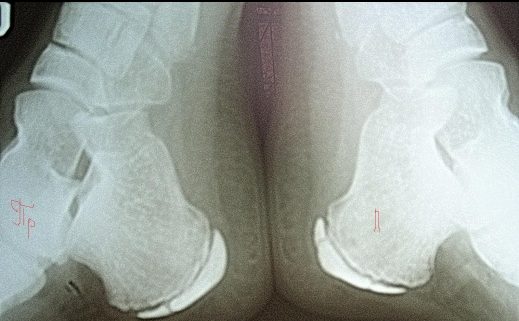

Остеохондропатия

В области пятки наблюдаются отек, припухлость и покраснение. Причинами могут быть нарушения работы эндокринных желез, травмы или нехватка кальция. Чаще всего такие проблемы возникают у девочек в возрасте 11–12 лет. Врач может рекомендовать рентгенографию, массаж и физиотерапевтические процедуры. При адекватном лечении симптомы обычно исчезают в течение двух месяцев.

Болезнь Шинца

Заболевание чаще всего встречается у мальчиков в возрасте 9–10 лет и у девочек 7–8 лет. В области пяточной кости нарушается процесс окостенения, что вызывает дискомфорт при ходьбе. Кожа может покраснеть, появляется отек, а температура тела повышается. Основные причины включают заболевания сердечно-сосудистой системы, генетическую предрасположенность и физические нагрузки. Врач проводит осмотр, назначает рентгенографию и, при необходимости, фиксирует голеностопный сустав с помощью гипса. В некоторых случаях могут быть рекомендованы процедуры, такие как электрофорез, ультразвук и другие физиотерапевтические методы.